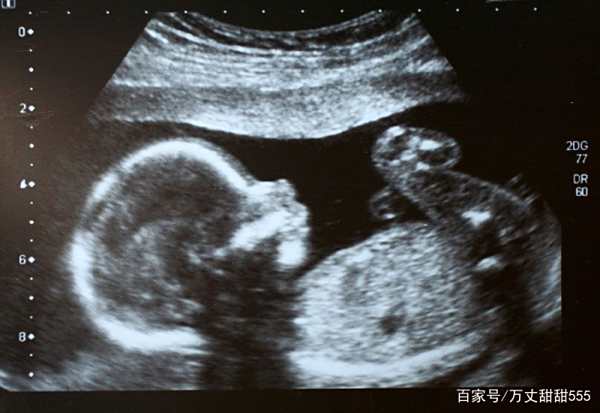

姗姗怀孕6个月的时候去孕检,检查的医生是婆婆的熟人。婆婆就偷偷问人家孩子的性别,结果是两个女儿,婆婆的脸色当时就变了。回到家后就对姗姗大不如以前,指示着姗姗做着做那,家里的鸡鸭鱼肉也收起来了,每顿只吃青菜。

医院的三维彩超、四维彩超、无创DNA、羊水穿刺等都能帮助我们检查出宝宝是否发育正常。

早孕期检查可在10周前或11-14周去做染色体软指标、初步形态学筛查、双胎绒毛膜性判断;中孕期检查可在20-24周做系统性超声筛查;晚孕期检查可在28-34周进行补漏筛查和生长发育检查。